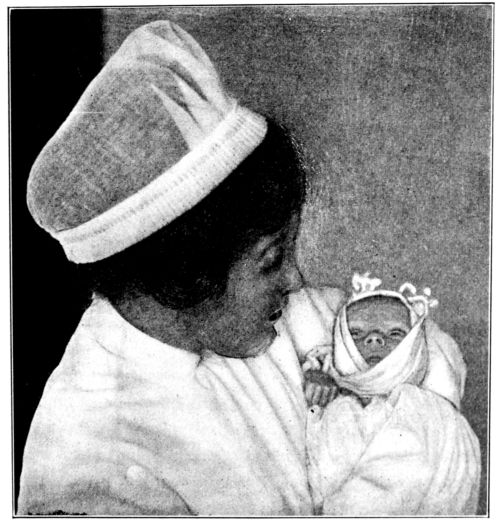

| 167. | Proper method of carrying baby | 487 |